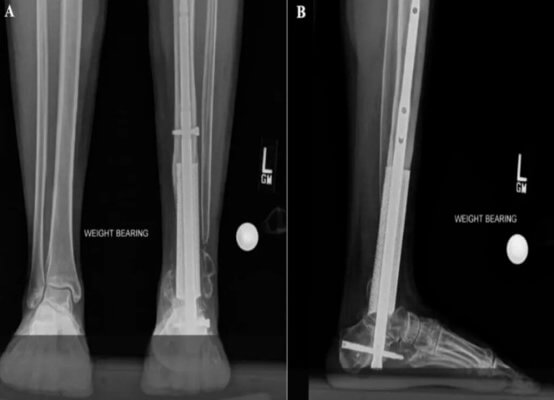

Der 3D-Käfig wurde speziell für den Patienten entworfen und aus Titan gedruckt. Der Käfig wurde dann während einer Operation in den Defekt eingesetzt, um die Regeneration von Knochengewebe zu ermöglichen.

Die Operation war ein Erfolg und der Patient erholte sich schnell von dem Eingriff. Der 3D-gedruckte Käfig erwies sich als stabil und konnte den Heilungsprozess unterstützen.